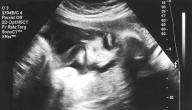

• فحص الموجات فوق الصوتية: يعمل الجهاز الذي يستخدم هذه الموجات بالاستعانة بماسحة ضوئية خاصة بتكوين صورة للجنين، وهي طريقة شائعة للكشف عن الحمل، كما يُستخدَم اختبار هذه الموجات المهبلي للحصول على صورة واضحة للجنين خلال المراحل المبكرة من الحمل.